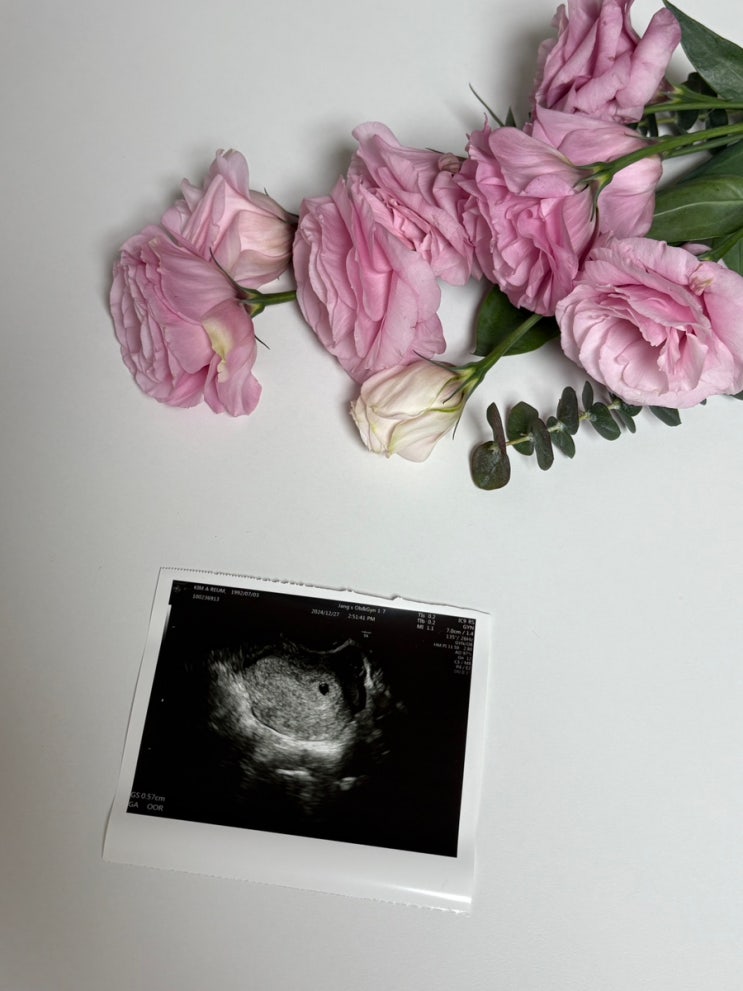

임신 8주 - 10주 증상 초음파 기록 조리원 예약 양가 임밍아웃

임신 초기가 가장 조심해야 할 때라는데 거의 매주 주말마다 이벤트가 끊이지 않던 주간이었다. 원래 집순...